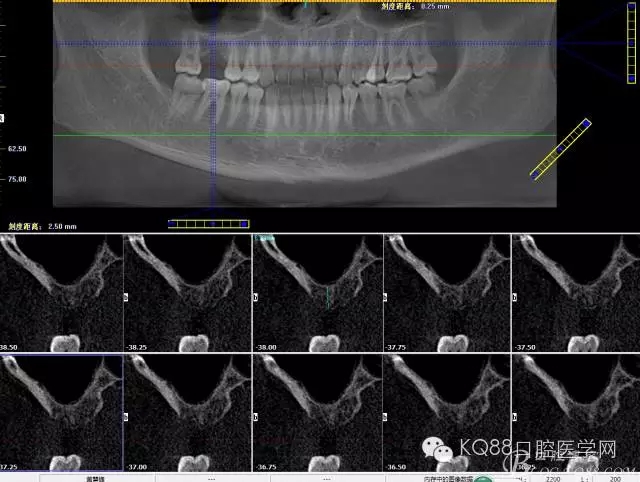

下面是拔牙后三個(gè)月的CBCT。垂直骨高度約6.7mm。

另外一個(gè)切面。垂直骨高度不夠,準(zhǔn)備 :做內(nèi)提升,植骨,植入植體。

植入后,CBCT

另外一個(gè)切面。竇底粘膜完整連續(xù)??梢钥吹缴舷乱Ш系奈恢藐P(guān)系。